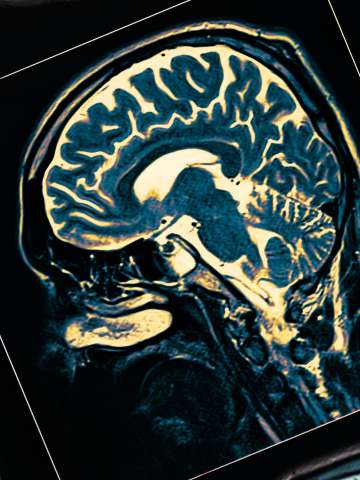

Our fellowship-trained cerebrovascular surgeons use the most sophisticated techniques to safely and effectively treat a variety of cerebrovascular conditions.

Receiving a diagnosis of cerebrovascular disease can be frightening, and chances are you have a lot of questions and concerns. UCLA Health understands this and we are here to help. If you have a vascular disorder of the brain – also called a cerebrovascular disorder – where you go for treatment is crucial. These conditions require surgeons who have the skill and expertise to manage them effectively. And that’s exactly what you can expect from the UCLA cerebrovascular team.

Our team of experts provides each patient with a comprehensive evaluation, imaging and other diagnostic testing. We then formulate a customized treatment plan. Conditions that we treat include: